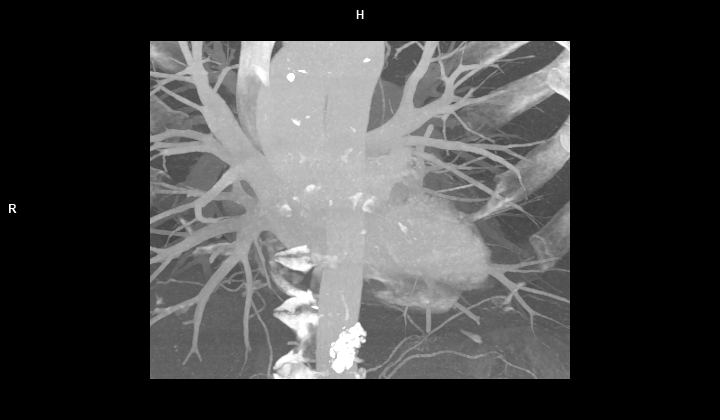

Figura 2: imagine MIP (maximum intensity projection) în plan coronal din achizitie CT fără contrast